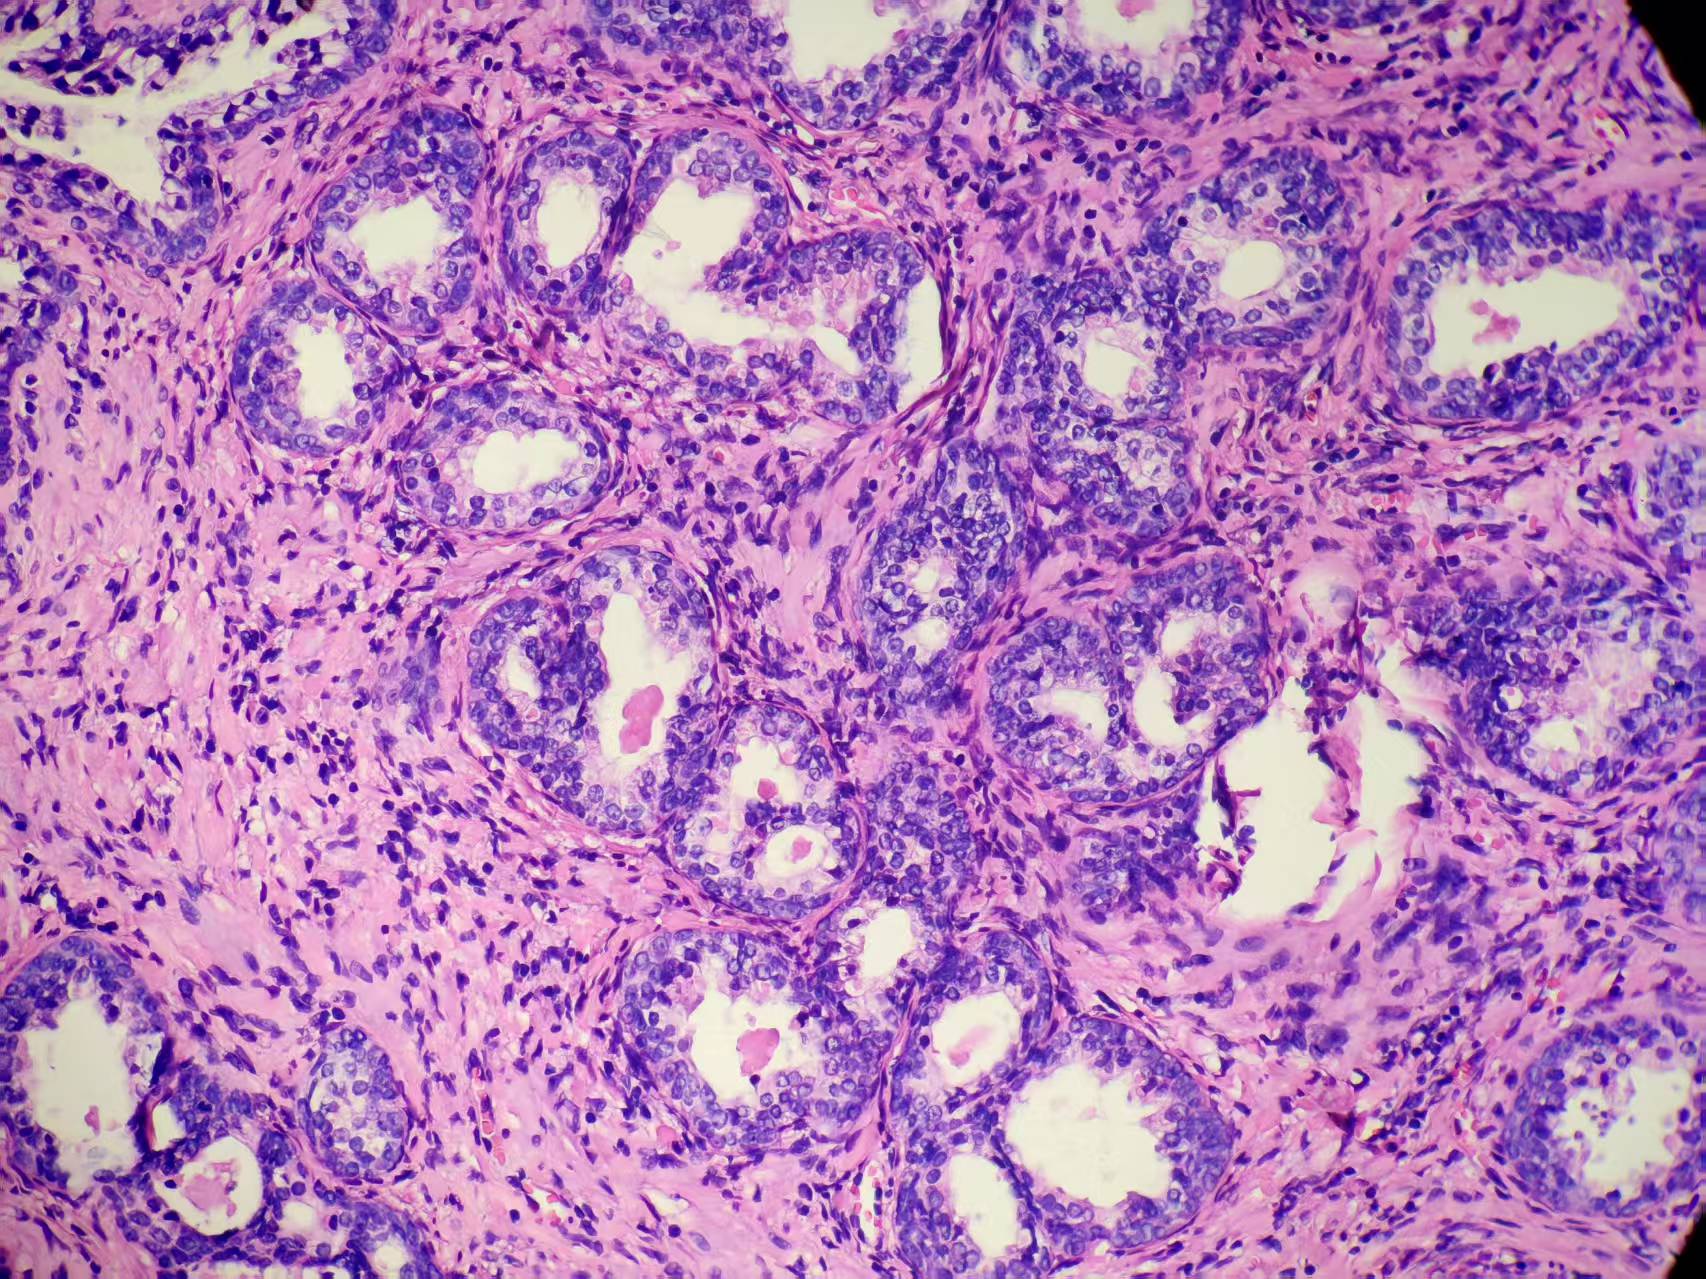

前列腺PIN?

发现肉眼血尿5月余,PAS 5.7

本例核仁巨大,值得关注!

嗜酸性大核仁,胞浆透亮,PIN没问题。还是组化一下吧,

zhuang xia nan:

标记一下,除外更重病变。